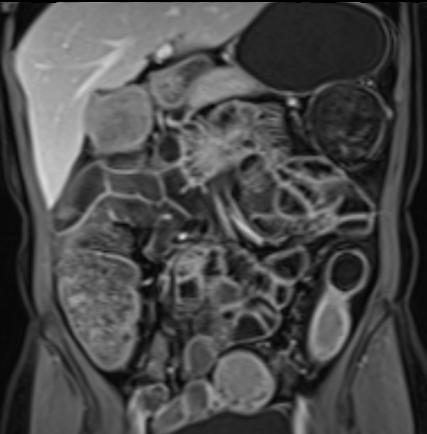

Phát hiện hẹp lòng ruột ở đại tràng sigma, không thể vượt qua được khi nội soi.

MR-enterography được thực hiện để đánh giá mức độ lan rộng của chỗ hẹp.

Ruột non bình thường, nhưng ghi nhận các đoạn hẹp ở đại tràng xuống và đại tràng ngang.

Cả hai đoạn hẹp đều có thành ruột dày đến 8 mm và ngấm thuốc rõ rệt theo kiểu niêm mạc ở đại tràng xuống và kiểu phân lớp ở đại tràng ngang.

Giãn ruột trước chỗ hẹp được ghi nhận ở cả hai đoạn.

Do các chỗ hẹp này không hiện diện khi nội soi đại tràng trước khi điều trị kháng TNF, nhiều khả năng chúng đã hình thành trong quá trình điều trị.

Do đó, quyết định phẫu thuật cắt đại tràng gần toàn bộ với miệng nối hồi-sigma đã được đưa ra.